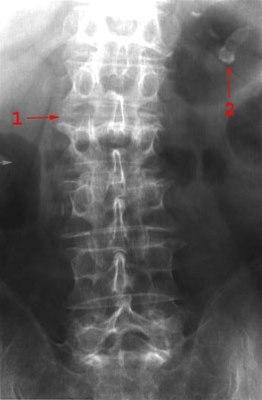

Ulike bruddtyper

Ulike bruddtyper kan oppstå:

- Kompresjonsbrudd

- Betyr at selve virvelen er blitt presset sammen i lengderetningen (se illustrasjonene over). En bruddtype som er vanlig ved beinskjørhet, og som vanligvis er et stabilt brudd.

- Tverrtagg-avriving

- Skyldes ofte et plutselig og sterkt drag i et muskelfeste. Selv om slike brudd virker uskyldige, kan de forårsake større blødninger.

Røntgen kan avklare diagnosen. Ved mistanke om instabilitet og ved nakkeskader tas CT. MR tas kun ved behov for bedre bilder av ryggmargen og leddbånd.